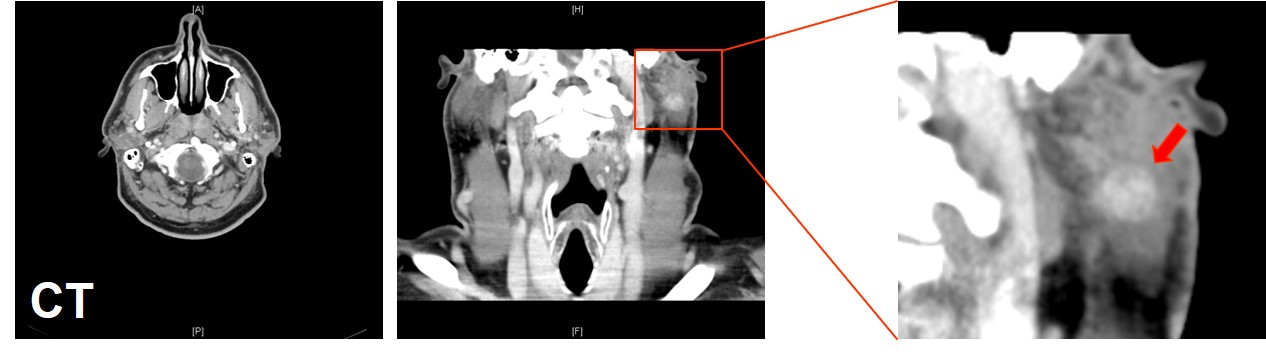

Computertomographie Kopf-Hals

Suspekte Läsion intraparotideal, links